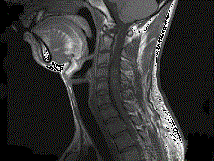

问题 男,24岁,颈部疼痛,并右上肢麻木,以手部明显,请根据所提供图像,选择最可能的诊断 ( )

选项 A、(颈4~5)血管母细胞瘤 B、(颈4~5)胶质瘤 C、(颈4~5)脊膜瘤 D、(颈4~5)海绵状血管瘤 E、(颈4~5)神经鞘瘤

答案 E